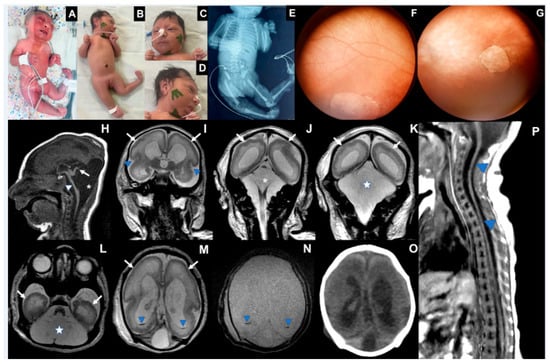

3.2. Case 2 (Figure 2)

| Microcephaly/Craniofacial disproportion/Skull collapse/short neck | Yes | Yes | Yes |

| Arthrogryposis multiplex | No | Yes | Yes |

| Fetal hydrops | No | Yes | Yes |

| Neurologic findings | Hypotonia, deep tendon hyperreflexia, dystonia, and epileptic seizures | Severe hypotonia (flaccid paralysis), no primitive or deep tendon reflexes, lack of suction, slow swallowing | Hypotonia, no deep tendon reflexes, lack of suction, slow swallowing |

| Ophthalmological findings | Visual impairment and nystagmus at 3 months | Corneal edema, optic disc atrophy, and chorioretinal scar in OU | Optic disc pallor and increased disc cupping (OS), chorioretinal macular scar and focal pigment mottling (OU), and vascular attenuation (OS) |

| Brain and Spinal Cord Images | Overlapping sutures, marked cerebral atrophy, partial lissencephaly, absent corpus callosum, brain cysts (cystic encephalomalacia and/or chronic subpial hemorrhages), subdural effusion, suspected striatal fusion, normal posterior fossa, normal spinal cord | Overlapping sutures, marked cerebral atrophy, absent corpus callosum, diffuse lissencephaly, severe brainstem and cerebellar hypoplasia, brain cysts (cystic encephalomalacia and/or chronic subpial hemorrhages), subdural effusion | Overlapping sutures, moderate cerebral atrophy, hypoplastic corpus callosum, diffuse lissencephaly, severe brainstem and cerebellar hypoplasia with Dandy–Walker-like features, intraventricular hemorrhage Global thinning of the spinal cord, mainly on the thoracic segment |